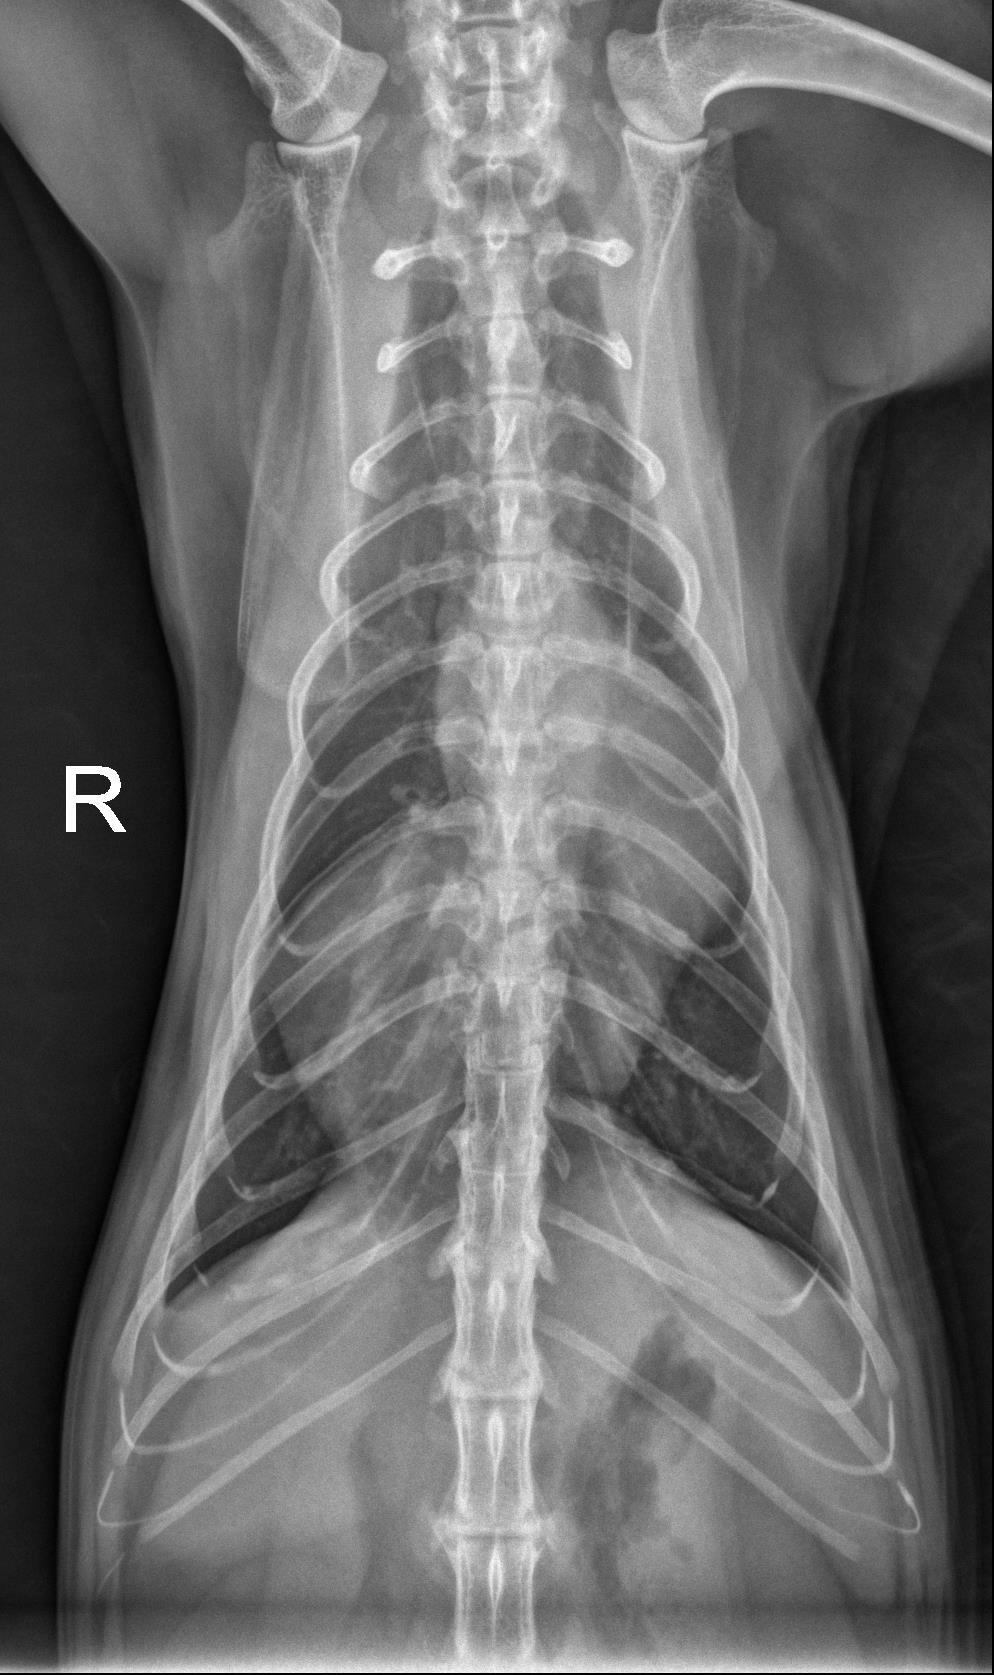

Orthogonal radiographs of the thorax are available for interpretation.

Within the caudal ventral thorax, directly adjacent to the diaphragm, there is a large, round, smoothly marginated, fat opaque structure that is causing dorsal and leftward deviation of the cardiac silhouette. The margins of the cardiac silhouette are distinctly identified superimposed with this structure on the lateral views.

The cardiac silhouette is normal in size. The pulmonary vessels, pulmonary parenchyma, and pleural space are normal.

The rounded structure in the caudal ventral thorax is suspected to represent fat opaque material and may be due to herniation/eventration of falcifom fat.

On the annotated image the cardiac margin remains visible when superimposed with the caudal structure. This indicates that those two are not of the same opacity. Furthermore the caudal structure is slightly more radiolucent compared to the cardiac outline.